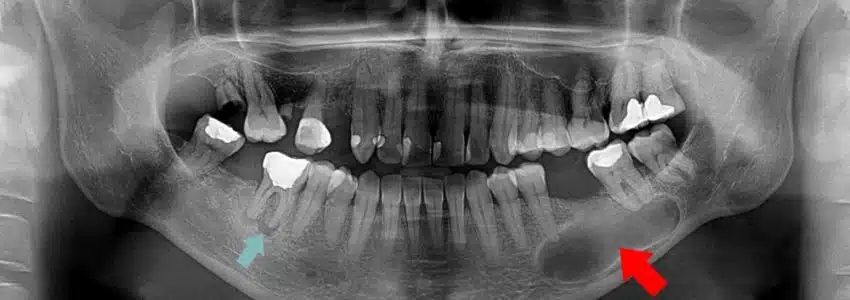

تصویر برداری

عکس برداری با اشعه ایکس انجام می دهند. این عمل به خاطر دریافتن این موضوع است که بدانید تا چه حدی ریشه دندان شما مورد آسیب واقع شده است. و پزشک معالج تا چقدر میخواهد این ریشه ها را درمان کند.